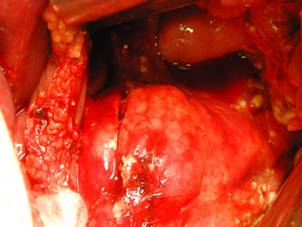

Leziune de lob drept hepatic prin

impuscare Leziune de lob drept hepatic prin impuscare

Leziune hepatica

prin impuscare Leziune

hepatica prin impuscare